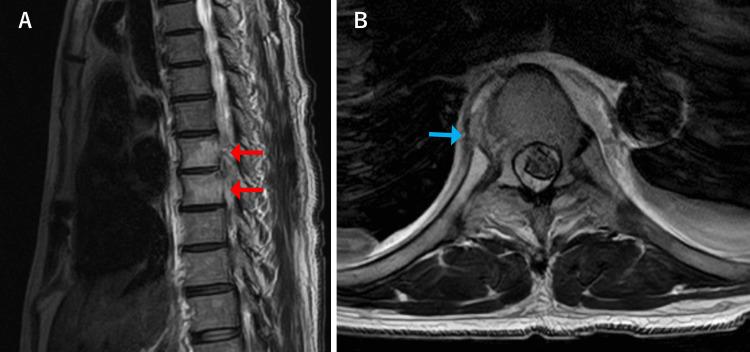

Pyogenic spondylitis typically presents with back and neck pain, fever, and fatigue. Sharp chest pain upon deep breathing, commonly associated with pleurisy, is not a typical manifestation of pyogenic spondylitis. We report a case of pleuritic chest pain as the initial presentation of pyogenic spondylitis. A 62-year-old male patient presented with a one-week history of right-sided pleuritic chest pain and fever. Chest computed tomography (CT) revealed a right pleural effusion. The patient was initially treated for bacterial pleurisy without improvement and subsequently developed back pain. Blood cultures yielded methicillin-resistant ( ​​​​). Additional thoracic spine magnetic resonance imaging (MRI) demonstrated pyogenic spondylitis with abscess formation on the right side of the vertebral body. The final diagnosis was pyogenic spondylitis that had progressed and spread inflammation to the pleura. This case highlights that pyogenic spondylitis can cause secondary pleurisy due to extension of inflammation to adjacent structures, a possibility that should be recognized. When  bacteremia is detected during the course of pleurisy, clinicians should consider secondary pleurisy and perform imaging studies to evaluate for pyogenic spondylitis.

摘要

化脓性脊柱炎通常表现为背部和颈部疼痛、发热及乏力。深呼吸时出现的尖锐胸痛,通常与胸膜炎相关,并非化脓性脊柱炎的典型表现。我们报告一例以胸膜炎性胸痛为首发表现的化脓性脊柱炎病例。一名62岁男性患者,有一周右侧胸膜炎性胸痛及发热病史。胸部计算机断层扫描(CT)显示右侧胸腔积液。该患者最初按细菌性胸膜炎治疗但无改善,随后出现背痛。血培养检出耐甲氧西林(此处原文缺失内容)。额外的胸椎磁共振成像(MRI)显示化脓性脊柱炎,椎体右侧有脓肿形成。最终诊断为化脓性脊柱炎,炎症进展并蔓延至胸膜。该病例强调化脓性脊柱炎可因炎症蔓延至相邻结构而导致继发性胸膜炎,这一可能性应得到认识。当在胸膜炎病程中检测到菌血症时,临床医生应考虑继发性胸膜炎并进行影像学检查以评估是否存在化脓性脊柱炎。